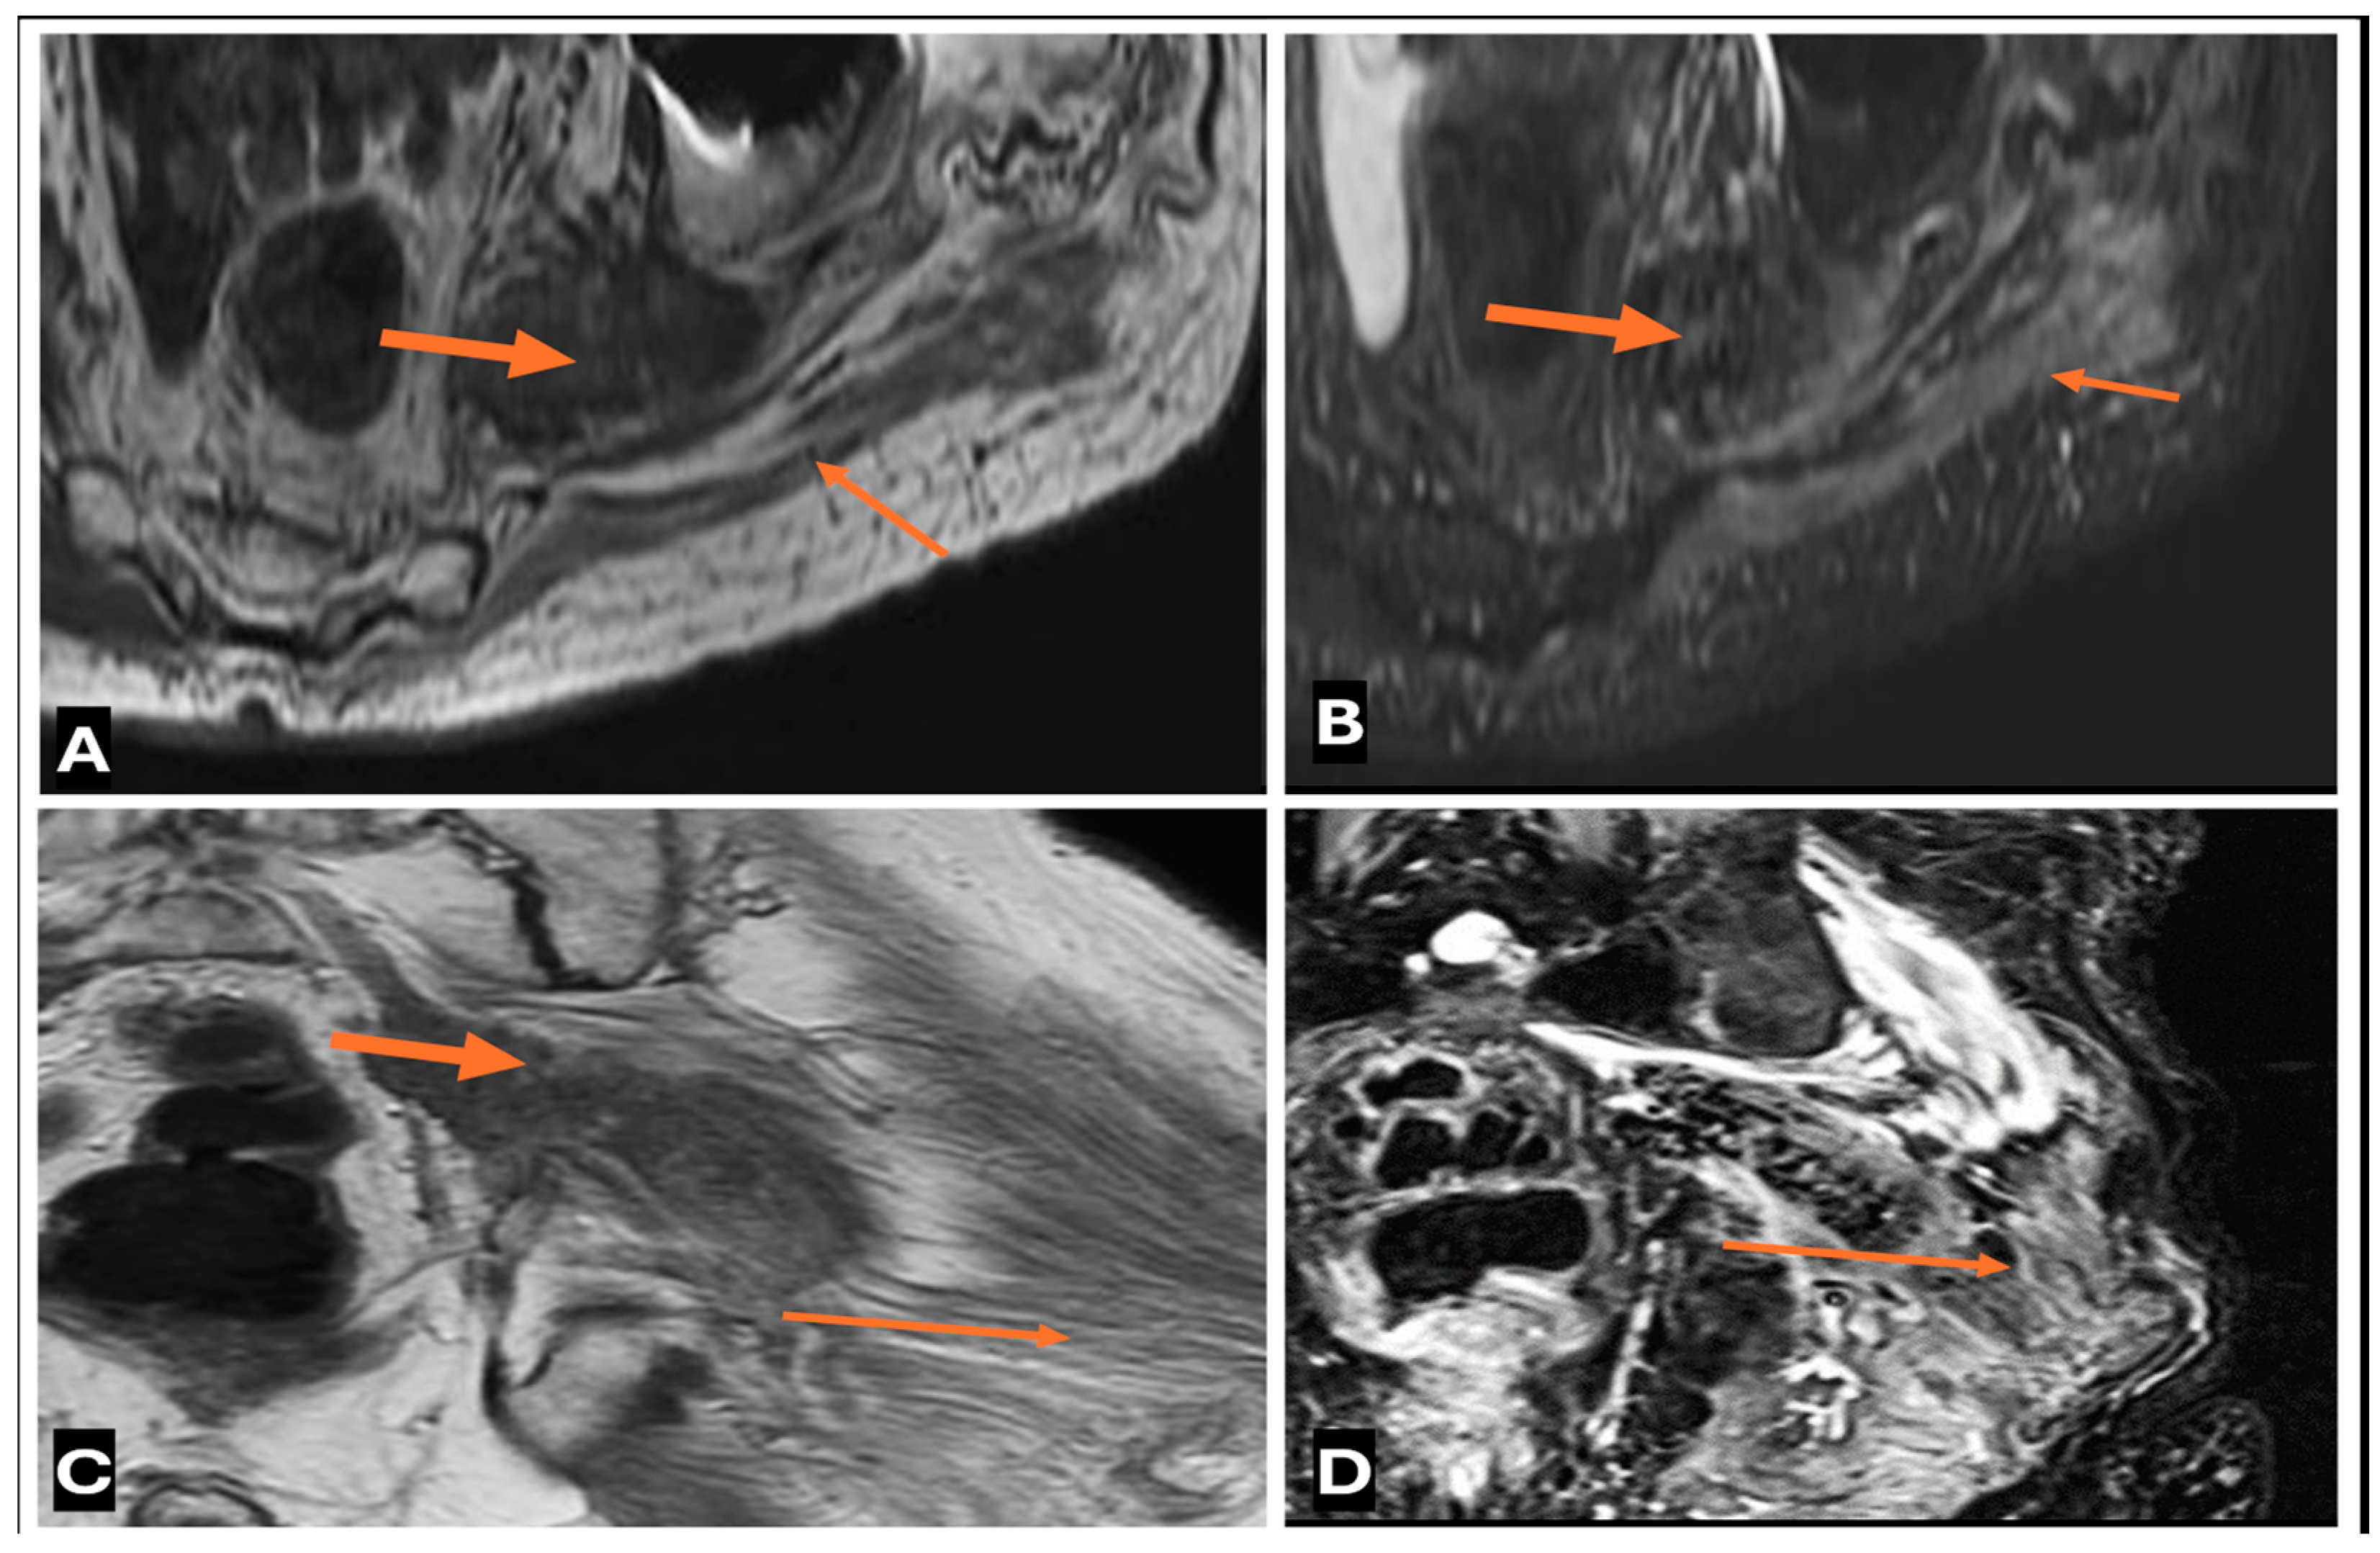

- Primary Sarcomas: Soft-tissue sarcomas are uncommon, accounting for just over 1% of adult malignancies. Synovial sarcoma, clear cell sarcoma, and epithelioid sarcomas are known to involve peripheral nerves. CT/MR reveals a large soft tissue mass with areas of necrosis or calcification and heterogeneous contrast enhancement. F-18 FDG uptake is useful for both tumor staging and treatment assessment (Figure 26, Figure 27 and Figure 28).